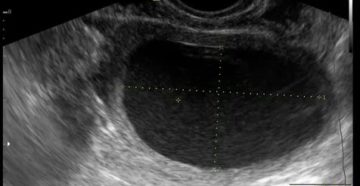

Как делают УЗИ на определение кисты яичника и как разные виды выглядят на мониторе ›…